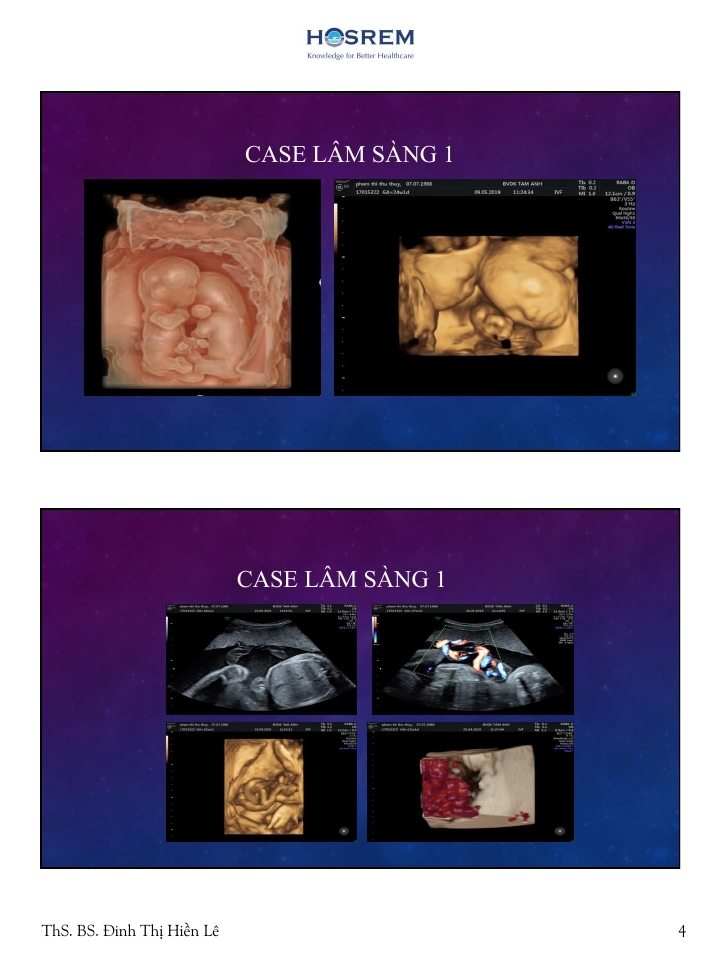

Song thai một buồng ối- một bánh rau

Từ khóa: Song thai một buồng ối- một bánh rau